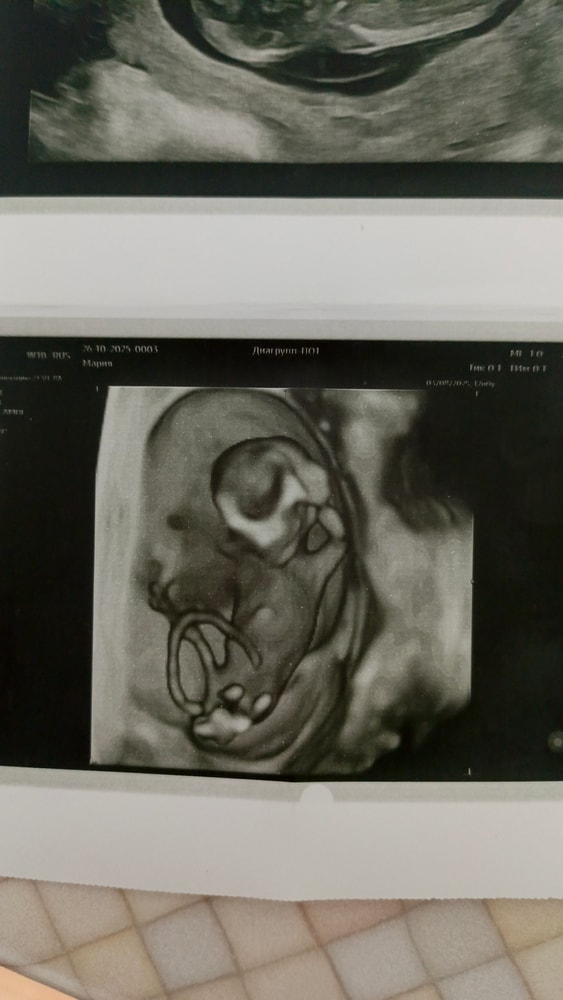

На кого похож?

Объясните что на первом фото внизу ?